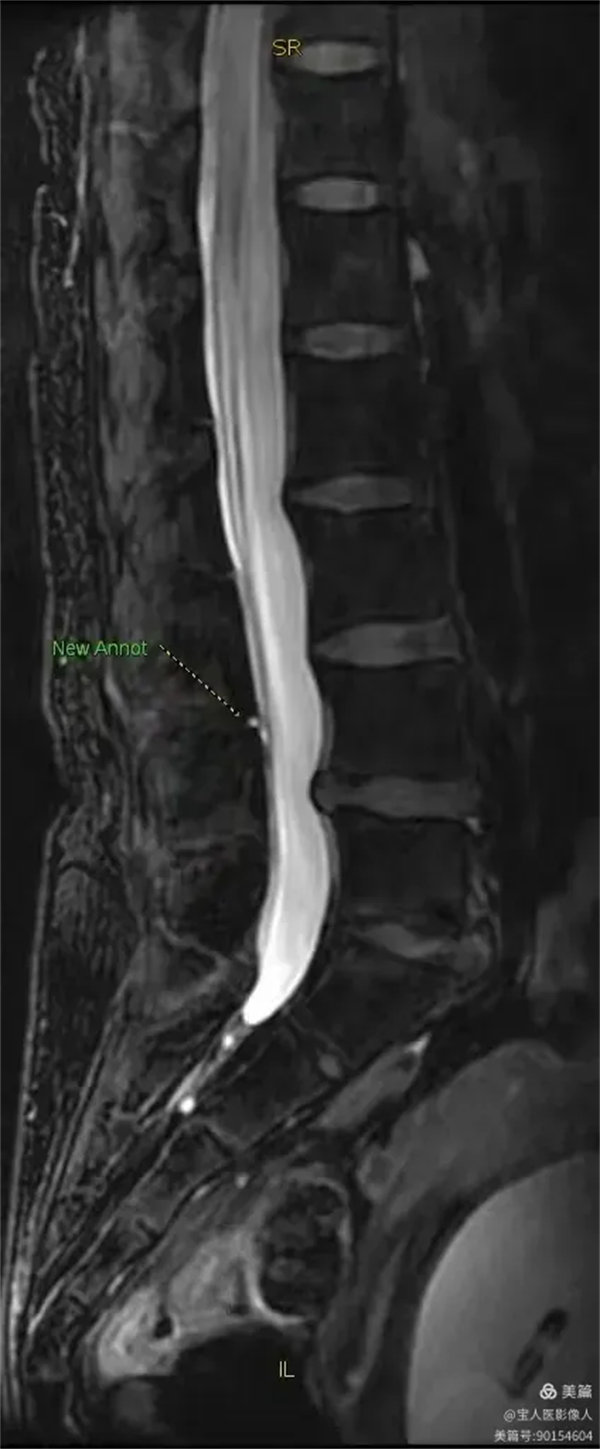

最大密度側面圖,顯示腰段硬膜囊內腦脊液(高信號)。

最大密度側面圖,顯示腰段硬膜囊內腦脊液(高信號),前方的椎間盤受壓弧形凹陷,后方的局部膨出。